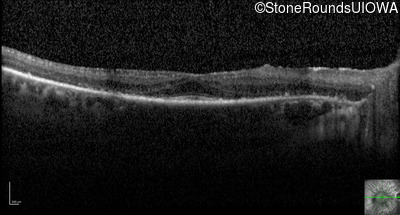

Optical Coherence Tomography - Right - 20/50 +1

Exemplar / OCT Stack

OCT Stack